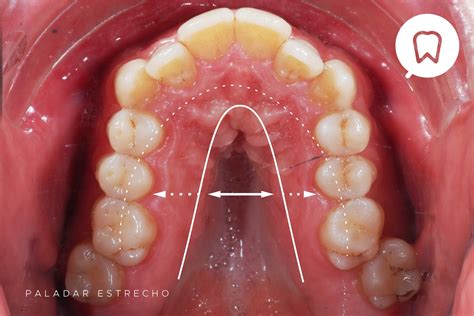

Los dientes normalmente erupcionan dentro de las encías. A veces, por razones genéticas o falta de espacio en el maxilar, un diente aparece en el lugar equivocado, como en el techo de la boca.

Cuando los caninos de la arcada dental superior no erupcionan alrededor de los 12 años, hablamos de canino incluido en el paladar, canino incluido por palatino o, como muchos pacientes le llaman, “caninos cruzados en el paladar”. En su lugar permanece el canino de leche y suele pasar desapercibido por el paciente hasta que el canino de leche se mueve o se cae en la edad adulta.

En la mayor parte de los casos las causas de origen genético son las responsables del problema. Algunas teorías lo relacionan a su desarrollo en el tiempo. El canino superior es el diente con el tiempo de formación más largo, se forma en una zona muy alejada y profunda, tiene con un camino largo de erupción y además es el último en erupcionar en la arcada dentaria.

Otras posibles causas del canino incluido son la ausencia de reabsorción de la raíz del canino de leche (que también podría ser el resultado del canino incluido), alteraciones del germen dentario, el cierre prematuro de la raíz y el apiñamiento dental.

La falta de espacio en la arcada o la persistencia del canino temporal, habitualmente señaladas como causantes de la inclusión del canino, no son relevantes. Por un lado, las personas con CIP no suelen presentar limitaciones de espacio significativas en la arcada y, por otro, la persistencia del canino temporal es la consecuencia, y no la causa, de la erupción ectópica del canino definitivo.

Los colmillos montados aparecen cuando los caninos no erupcionan correctamente, quedando en una posición más elevada que el resto de los dientes. Uno de los motivos más comunes es la falta de espacio en la arcada dentaria. Cuando los dientes vecinos ocupan demasiado sitio, los colmillos pueden verse obligados a emerger en una posición más alta.